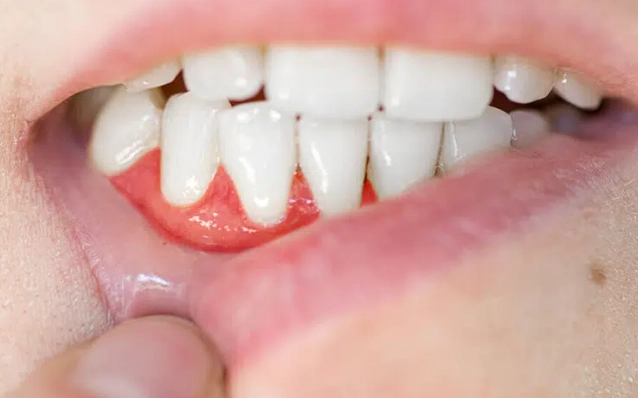

- 顏色與質地:健康的牙齦是粉紅色、有點像橘子皮表面的點狀顆粒、質地堅韌。如果萎縮的邊緣呈現鮮紅、一碰就流血、或顯得鬆軟,那可能表示仍有發炎,需要回診。